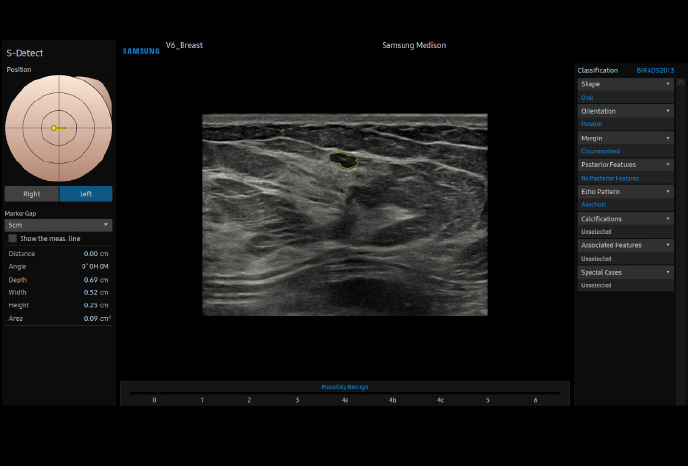

하이앤드 초음파 장비를

활용한 정밀 심장 검사

심장 질환 진단에서 가장 중요한 것은 ‘심장의 상태를 얼마나 정확하게 볼 수 있느냐’입니다. 저희 센터는 대학병원급 하이앤드 초음파 장비를 도입하여, 실시간 3D 렌더링으로 정밀 진단이 가능하며, 심장의 구조·혈류·기능을 실시간 고해상도로 관찰합니다.

미세한 판막 움직임, 혈류 속도 변화, 심방·심실 크기와 수축력까지 정밀하게 분석할 수 있어, 심장질환의 조기 발견과 치료 계획 수립에 큰 차이를 만듭니다.